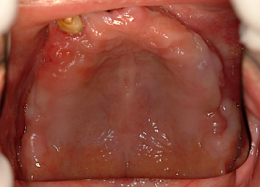

治療対象は、無歯顎(全く歯が無い方)、または残存歯がほとんど良くない方です